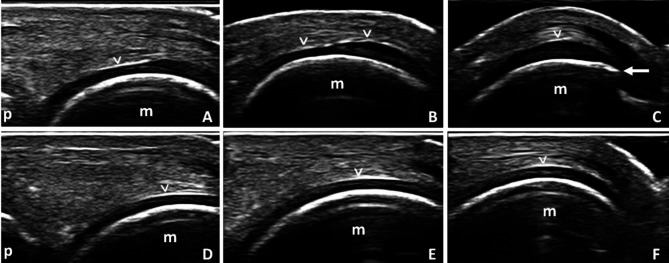

Objective: To determine whether the presence of conventional radiography (CR)-detected osteophytes is associated with focal thickening of the hyaline cartilage by ultrasound (US) in the same area of the metacarpal head in a within-person, between-joint cross-sectional comparison in patients with hand osteoarthritis (HOA).

Design: 64 patients with HOA (classified using the 1990 ACR classification criteria) were screened. Participants were eligible for inclusion if they displayed osteophytes in at least one of their metacarpophalangeal (MCP) joints, no osteophytes in the contralateral corresponding MCP joint and no joint space narrowing (JSN) in either MCP joint by CR. In these patients, cartilage thickness was measured by US in 2 subregions of both metacarpal heads (i.e., the central force-bearing and the proximal peripheral area). Location-specific association between osteophytes and cartilage thickness was evaluated.

Results: 14/64 (21.9%) patients and 23 pairs of MCP joints were included in the analysis. Metacarpal heads with osteophytes had significantly thicker hyaline cartilage than contralateral ones without osteophytes in the proximal peripheral area of the hyaline cartilage [0.78 mm and 0.66 mm, respectively (p < 0.01)]. On the other hand, no difference in terms of cartilage thickness was found between the metacarpal heads with osteophytes and the contralateral ones without osteophytes in the central force-bearing area of the hyaline cartilage [0.65 mm and 0.66 mm, respectively (p = 0.53)].

Conclusions: MCP joints with early radiographic HOA display thicker hyaline cartilage than contralateral MCP joints without radiographic signs of HOA, specifically in the proximal peripheral subregion of the metacarpal head.